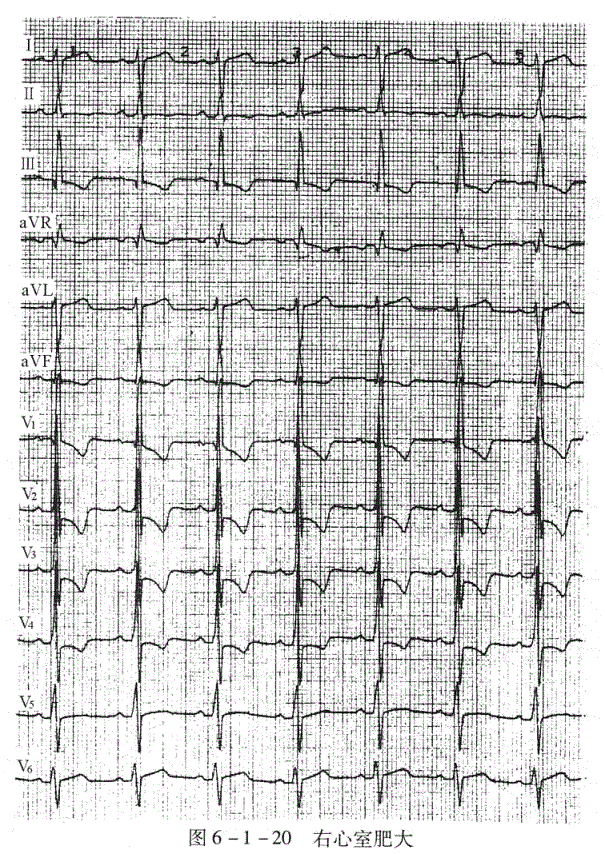

右心室肥大(图6-1-20):V

导联R/S≥1,V

导联R/S≤1或S波比正常加深,重度肥厚可使V

导联呈qR型(除外心肌梗死)。

RV

+S

>1.05mV(重症>1.2mV);aVR导联的R/q或R/s≥1,R波>0.5mV。心电轴右偏≥+90。(重症可>110。)。

图6-1-20右心室肥大

临床资料:男性,23岁。先心病,肺动脉重度狭窄。

心电图分析:P-R=148ms,QRS=104ms,QT/QTe=348/406ms。P、R、T电轴+5°、+120°、-23°,V

导联呈qR型,V

导联R波=3.0mV,V

导联R波=4.6mV,V

、V

导联以s波为主,显示右室肥厚的特征。

心电图诊断:①窦性心律;②右心室肥大。